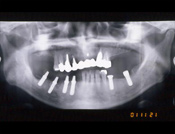

症例 18)

尚、下のレントゲン写真は向かって左側が患者さんの右側です。

ご注意下さい。左右反対な感じがするでしょうから。

2004年6月ボストンのPRDで発表した症例の方です。

初診時、右下奥歯が揺れていました。

植立手術後、右下奥歯が出来ました。

最終冠の状態、骨が再生しました。

症例提供:KMインプラント・松元歯科 松元教貢先生 無断転写はお断りします。